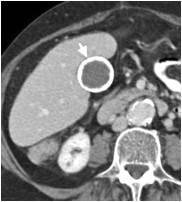

- בדיקת אולטרה-סאונד של כיס המרה (תצלום 1.8).

בדיקת האולטרה-סאונד היא מכשיר עזר חשוב באבחון הלוקים באבנים בכיס המרה, בצהבת או במצבים דלקתיים חריפים. אמינות הבדיקה היא גבוהה - 95%. בבדיקה זו מודגמות האבנים בכיס המרה כנקודות בהירות שמאחוריהן "צל אקוסטי" (Acoustic shadow) - אזור בלא החזרת קול (האבן חוסמת את הקול) (תצלום 1.8). אם הנבדק משנה תנוחה, האבן זזה, והדבר מודגם בבדיקה. אבנים בדרכי המרה ניתנות להדגמה ב- 20% מהמקרים. דרכי מרה מורחבות אפשר להדגים בלוקים בחסימה בדרכי המרה. בחולים אלה ההרחבה יכולה להיות של דרכי המרה החוץ ו\או התוך-כבדיות. (תצלום 2.8 ו- 3.8). נוזל סביב כיס המרה ודופן מעובה של כיס המרה מעידים על דלקת של כיס המרה (תצלום 4.8). אפשר לבצע בדיקת אולטרה-סאונד של דרכי המרה בזמן הניתוח ולאתר אבנים בדרכי המרה.